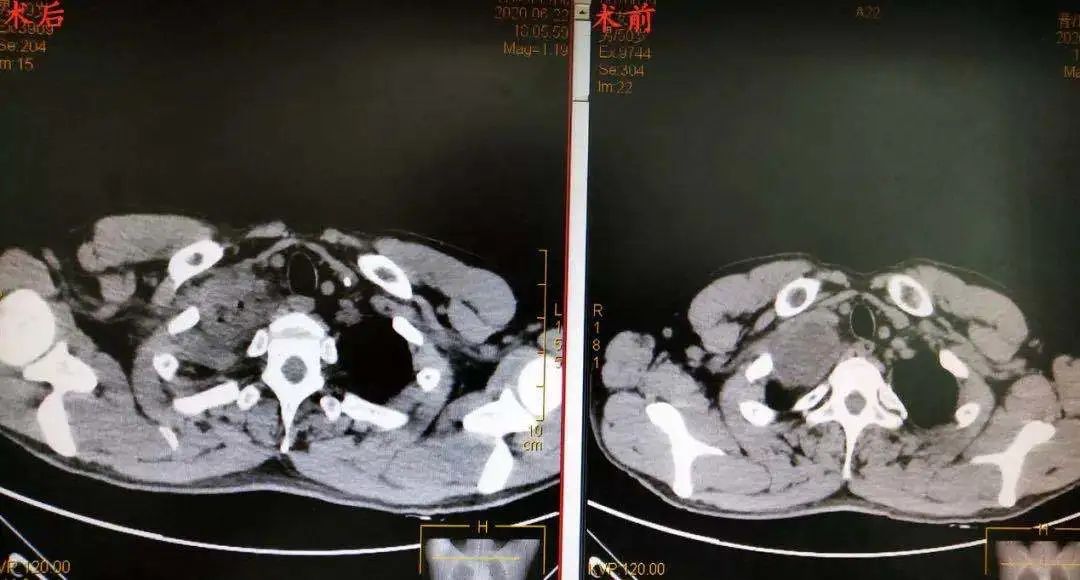

郑志民医生为苏先生进一步做了检查并询问了他的病史后,初步诊断为“右上纵隔巨大肿瘤,神经鞘瘤可能性大”,需要住院手术治疗。在苏先生住院进行了一系列检查后, 郑志民医生发现,他体内的肿瘤不仅体积大(直径约7cm),而且位置深(胸膜顶),紧邻大血管及右侧锁骨,手术难度大,遂决定向杭州的树兰医院胸外科朱理主任汇报并立即组织胸外科全科进行科内讨论。

手术当日,一场经过充分准备的“战斗”在手术室拉开序幕。在麻醉科的安全守护下,树兰医院朱理主任、晋医郑志民主任团队紧密配合,在两位主任强强联手下,在没有损伤到血管,没有劈开右侧锁骨、没有中转开胸的情况下,快速而巧妙地解决“战斗”。仅用时1个多小时,出血仅几毫升,切口3-4cm的微创手术下,患者右上纵隔肿瘤被完整切除,完成一场精彩的“探囊取物”。术后病理诊断证实与术前一致,为神经鞘瘤。

据郑志民主任医师介绍,苏先生的肿瘤巨大,且位置深,位于胸膜顶,紧邻大血管及右侧锁骨,这个位置的肿瘤对胸外科医生是一个巨大的挑战,锁骨切开是一个选择,但是考虑到手术如果采取切断锁骨的方式,会对锁骨的损伤非常大,手术风险性非常大,稍有不慎,就会损伤血管造成大出血的状况。这就要求主刀医生具有丰富的手术经验和过硬的显微外科技术。所幸在树兰医院朱理主任的助力下,经过1个半小时的努力,在微创下手术顺利完成,完成一个精彩的“探囊取物”。